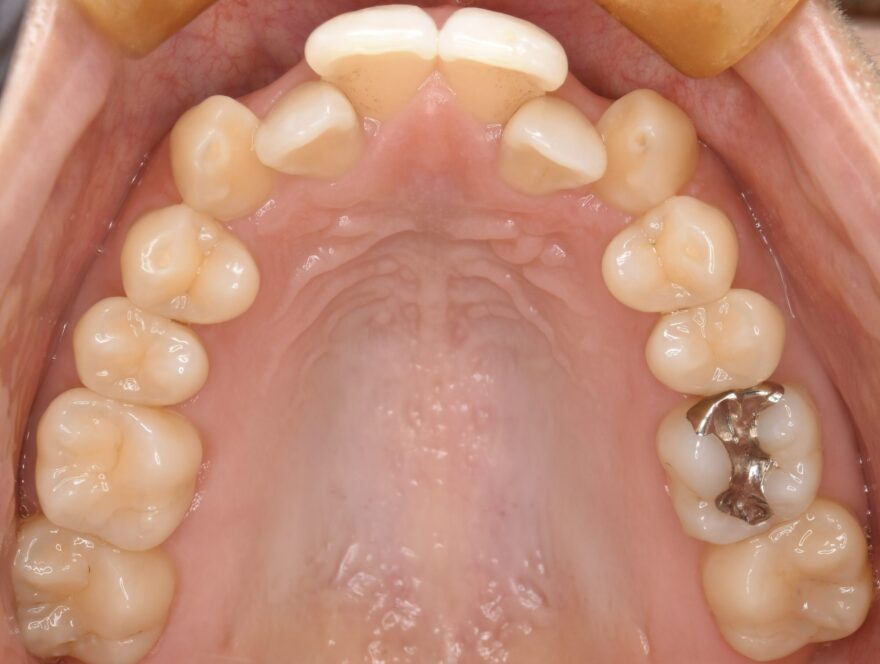

初診時の口腔内写真

上下の前歯のガタガタが気になります。

左上の2番目の前歯が、内側に引っ込んでいます。